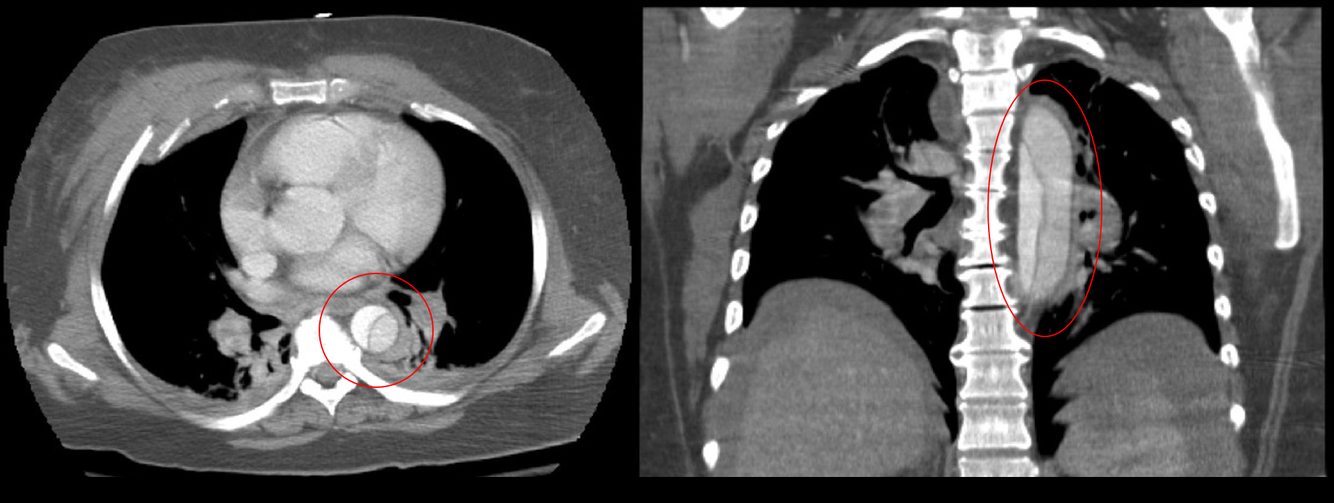

What is shown in the image?

CT Chest of Stanford Type B Aortic Dissection.

A computed tomography (CT) angiogram is recommended to diagnose aortic dissection as first line imaging. This will also allow classification, establish the anatomy of the dissection, and assist surgical planning.

Stanford Type A dissections should be managed surgically in the first instance and carry a worse prognosis than Type B dissections. Any uncomplicated Type B dissections can usually be managed medically.